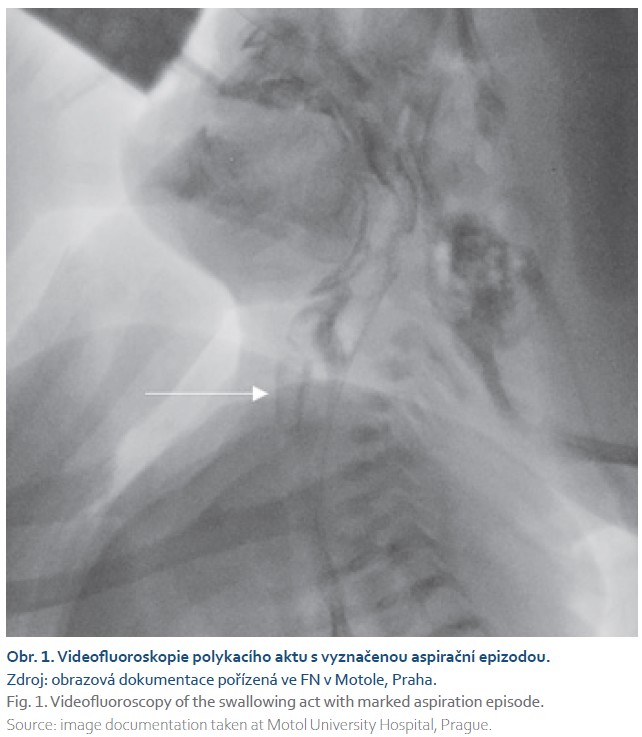

Po přeložení na naši kliniku jsme doplnili endoskopické vyšetření a videofluoroskopii polykacího aktu (FEES a VFS), kde byly přítomny masivní tiché postdeglutivní aspirace mléka z reziduí v hltanu při svalovém oslabení, na penetračně-aspirační škále odpovídající PAS skóre 8, netěsný velofaryngeální uzávěr (obr. 1).